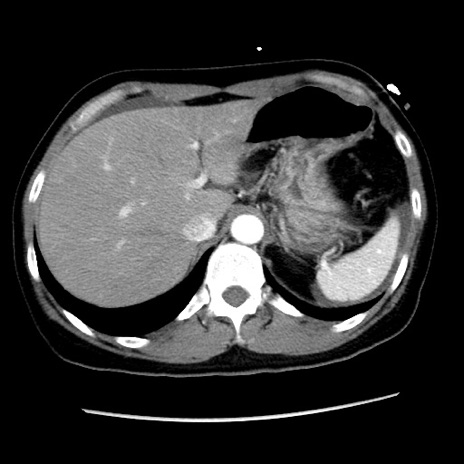

症例10(横断像)

【症例】 50歳代女性

【主訴】 腹痛

【現病歴】前日生レバーを食べた。今朝に排便あり。 昼前に突然発症の腹痛を生じ、当院救急外来を受診した。

【既往歴】 子宮筋腫にてで子宮全摘後

【身体所見】 意識清明、腹部:平坦、軟、下腹部やや左を中心に圧痛・反跳痛あり、筋性防御あり

【データ】WBC 7800、CRP 0.07